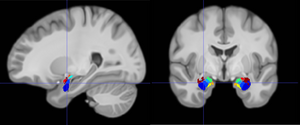

image: As participants encoded emotional words into memory (e.g., 'KNIFE'), fast brain oscillations increased in the hippocampus and amygdala. However, when they fail to encode emotional words, or encoded a neutral words (e.g., 'CHAIR'), these fast oscillations were smaller. view more

By systematically characterizing the emotional associations of each word using crowd-sourced emotion ratings, Qasim found that participants remembered more emotional words, such as “dog” or “knife,” better than more neutral words, such as “chair.” When looking at the associated brain activity, the researchers noted that whenever participants successfully remembered emotional words, high-frequency neural activity (30-128 Hz) would become more prevalent in the amygdala-hippocampal circuit. When participants remembered more neutral words, or failed to remember a word altogether, this pattern was absent. The researchers analyzed this pattern across a large data set of 147 patients and found a clear link between participants’ enhanced memory for emotional words and the prevalence in their brains of high-frequency brain waves across the amygdala-hippocampal circuit.